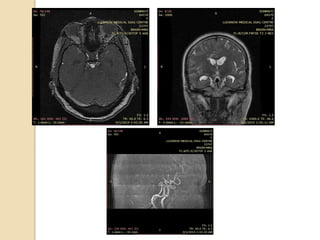

Bilobed aneurysm at Rt MCA bifurcation

3D TOF MRA demonstrates a 6 mm aneurysm arising

from the basilar artery tip and projecting anteriorly

3D TOF MRAdemonstrates a 6 mm aneurysm arising from the basilar artery tip and projecting anteriorly